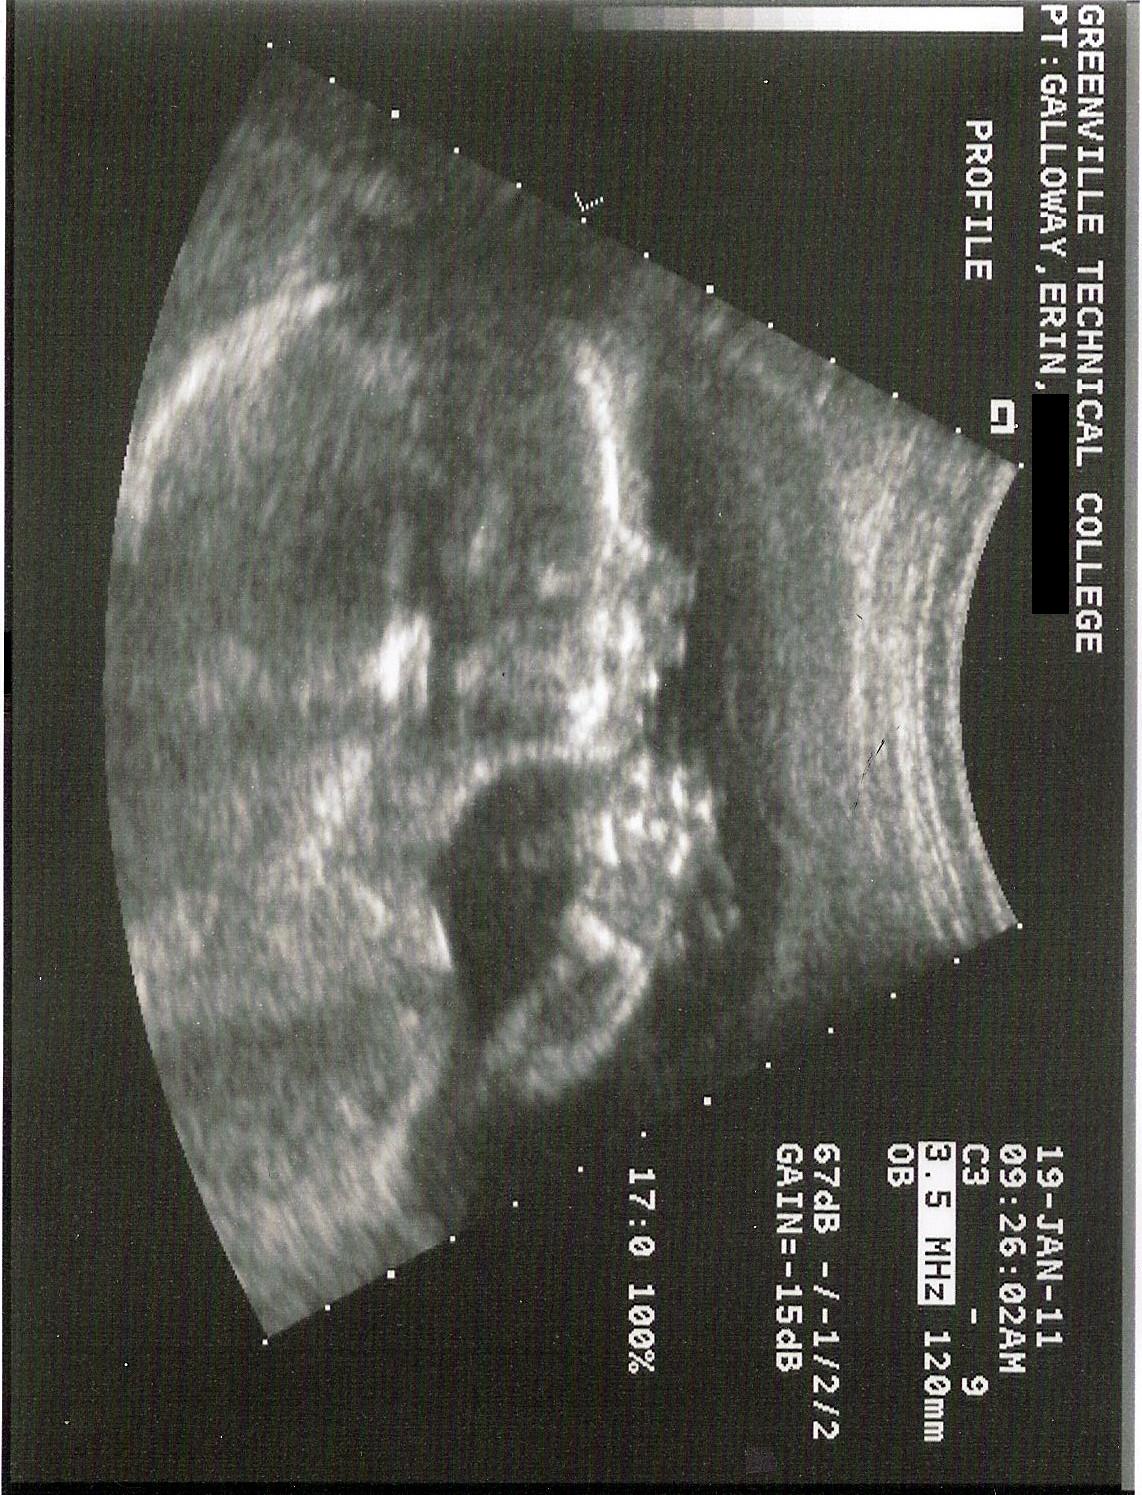

Here’s a profile view. I think she looks like Travis! The little circle under her chin is a cross section of her arm.